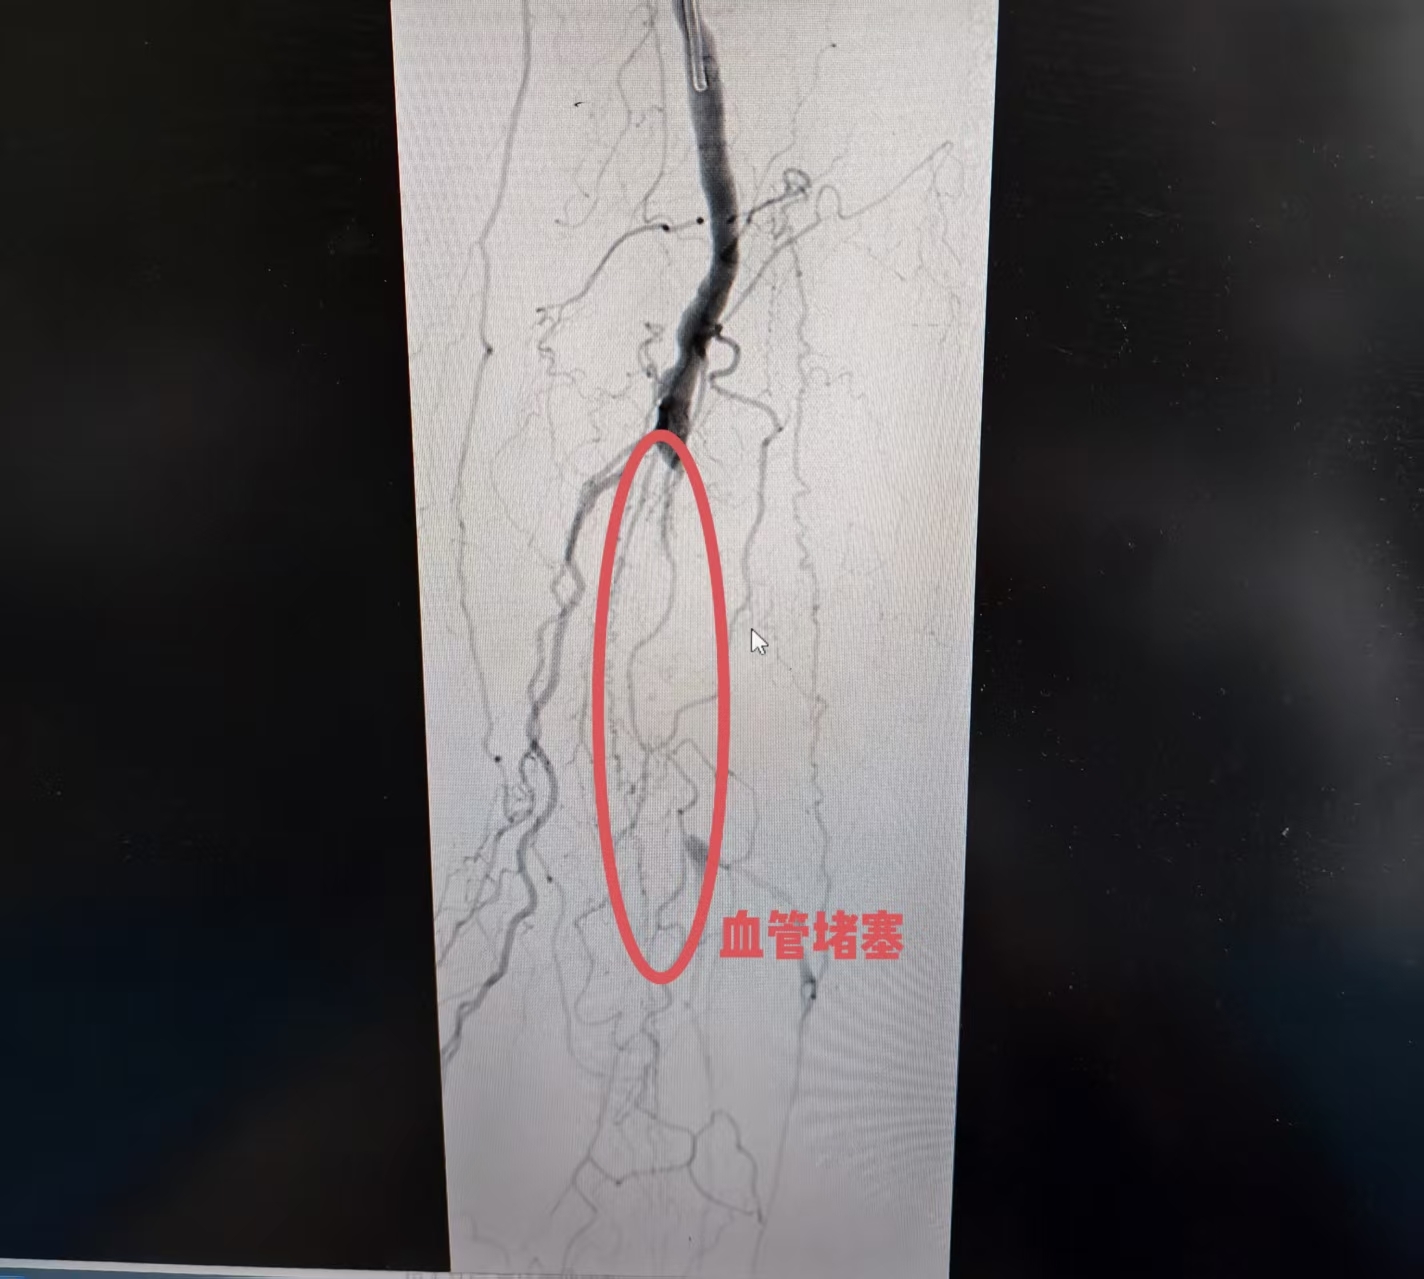

(堵塞的动脉血管)

今年79岁的袁爷爷(化名)患有糖尿病多年,半年前无明显诱因出现右下肢疼痛,同样出现了右足第二趾破溃,于是来到青岛市城阳人民医院血管外科就诊,相关检查显示双下肢动脉粥样硬化并多发斑块双侧股浅动脉闭塞,右侧胫前动脉节段性闭塞,诊断为“下肢动脉硬化性闭塞症、足溃疡”。

鉴于患者复杂情况,青岛市城阳人民医院血管外科张福涛团队立即邀请北大人民医院血管外科李清乐教授会诊,双方团队综合评估后认为,尽管风险存在,但通过微创技术,最大可能实现血管再通,保住患者脚趾。

团队为此制定了周密的手术预案,重点聚焦于开通对足部供血最为关键的闭塞段血管。按照原定手术方案,团队顺利为患者实施了“股动脉支架置入术、股动脉球囊血管成形术、动脉球囊血管成形术、下肢动脉造影”,术后,患者下肢血流恢复良好,疼痛症状消失,目前已康复出院。